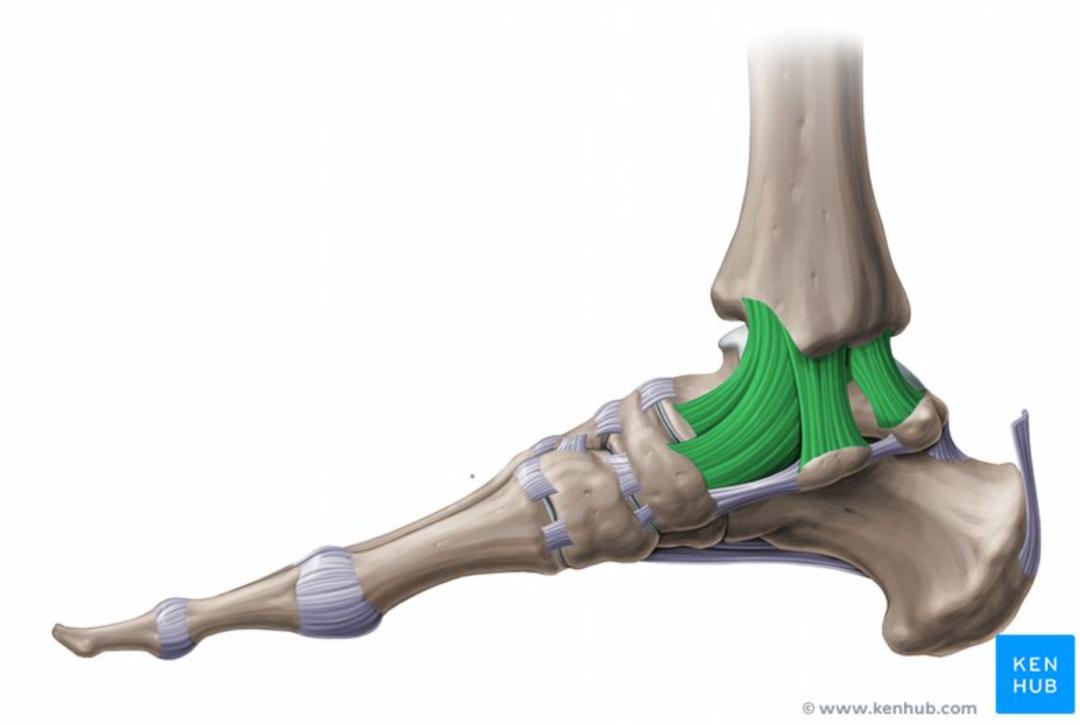

外侧副韧带(绿色标注)其次,维持踝关节稳定的"筋".